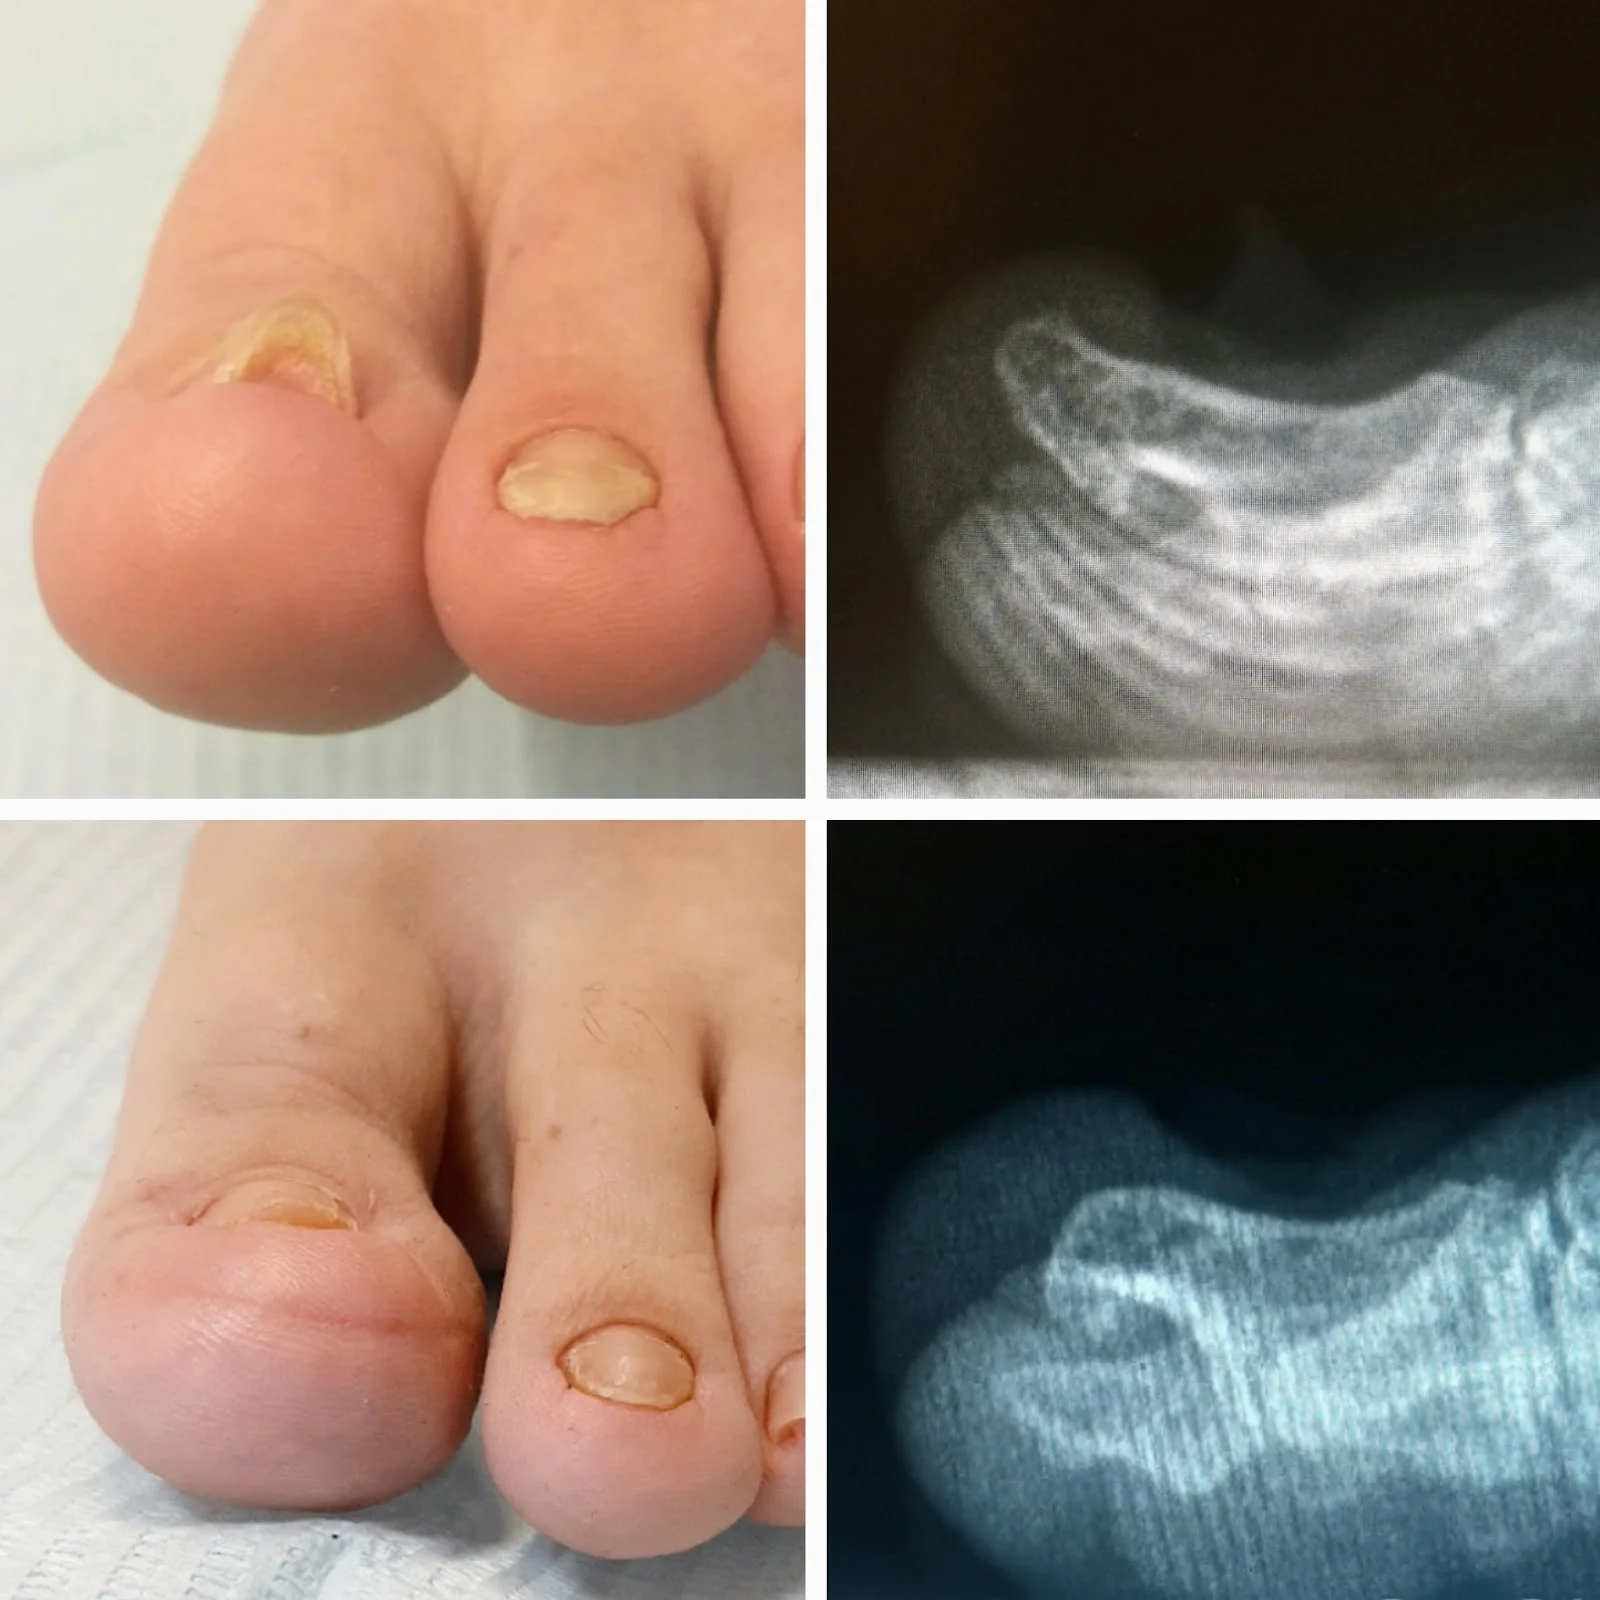

Lo que destaca a esta podóloga es su enfoque integral en la podología. Ofrece tratamientos para uñas encarnadas, callosidades, hongos y problemas biomecánicos, todo con técnicas modernas y productos de calidad. Los pacientes valoran su atención meticulosa y el ambiente acogedor que facilita cada visita. Además, con precios moderados, es una opción accesible sin comprometer la excelencia en fußpflege, o mejor dicho, en el cuidado especializado de los pies.

Entre sus ofertas concretas, destaca la entrada accesible para sillas de ruedas, lo que garantiza comodidad para todos los visitantes. Realiza revisiones preventivas, ortesis personalizadas y terapias para fascitis plantar, perfectas después de largas caminatas por las playas cercanas o el mercado de Manacor. Puedes esperar citas puntuales y recomendaciones prácticas para el mantenimiento diario de tus pies en el clima soleado de las Illes Balears.